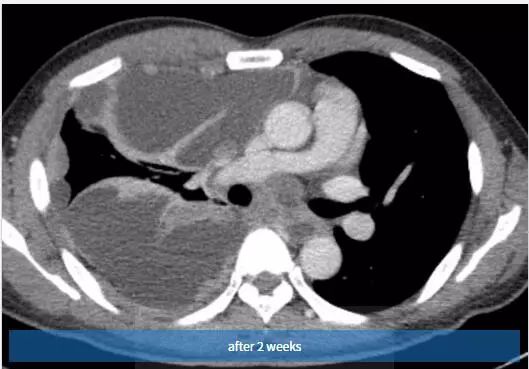

图3 2周后,随访胸片示右胸弥漫性阴影和胸腔积液。也可见引流管。

图4~6 2周内随访的对比增强轴位CT扫描示右半胸有大量多发性胸腔积液,弥漫性胸膜增厚和多灶性胸膜肿块。